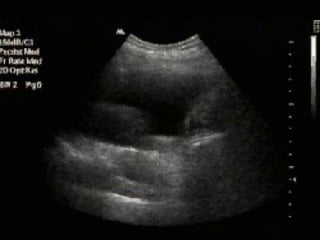

Tissue pattern representative of Alveolar

Consolidation

Presence of hyperechoic punctiform

images

imagesrepresentative of air bronchogramsrepresentative of air bronchograms

Pleural

effusion